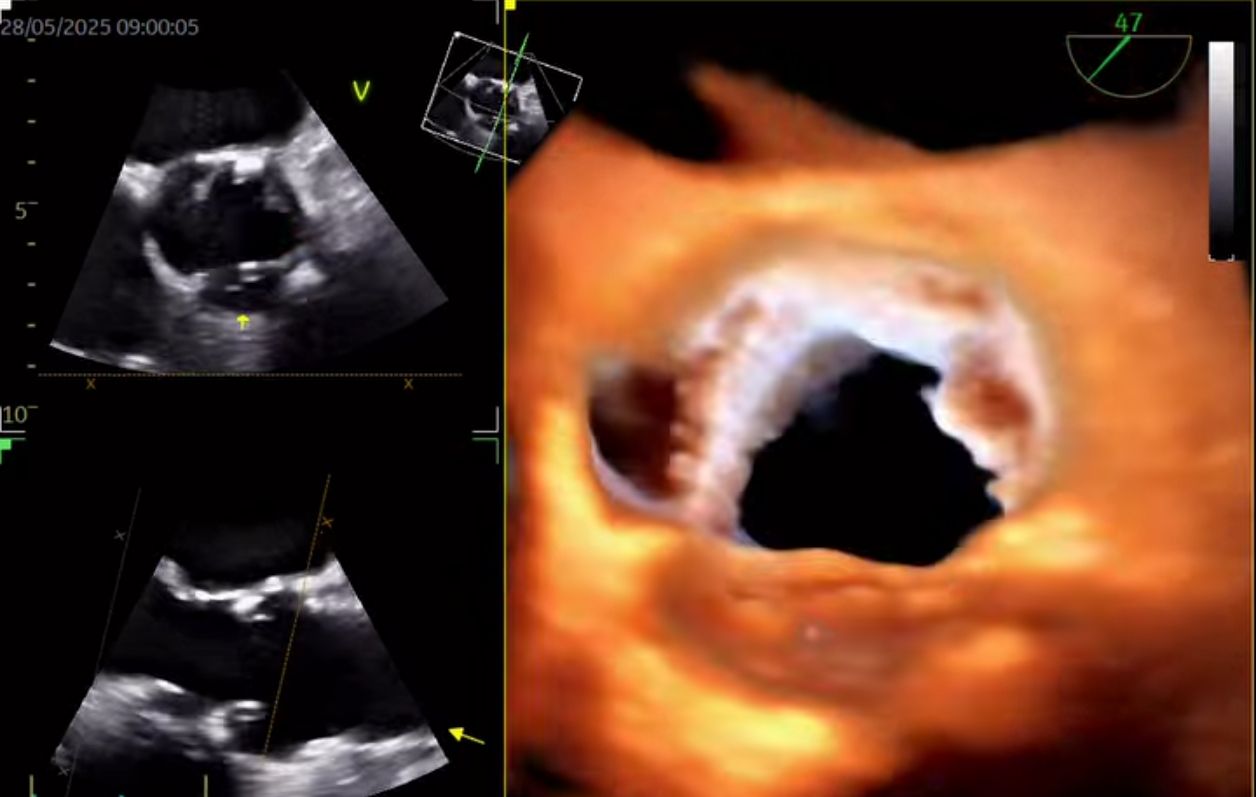

Soy el Dr. José Alberto Sánchez Toscano, con una subespecialidad en Cardiologia (2021-2023) y una alta especialidad en ecocardiografía transtoracico tridimensional en adultos (2024-2025). Egresado del Instituto Nacional de Cardiología "Ignacio Chávez" y certificado por el consejo mexicano de Cardiologia. Diplomado en Patología aórtica en la práctica clínica por la Universidad de Alcalá, Valencia 2023-2024).

Misión Profesional Como médico especialista en Cardiología y Ecocardiografía bidimensional y tridimensional, mi misión es brindar atención cardiovascular de alta precisión, combinando tecnología avanzada con un enfoque humano y personalizado. Me dedico a prevenir, diagnosticar y tratar enfermedades del corazón con excelencia médica, ayudando a cada paciente a comprender su salud cardiaca y tomar decisiones informadas. Busco generar confianza, bienestar y resultados concretos, promoviendo evaluaciones ecocardiográficas detalladas y confiables que pueden marcar la diferencia en el cuidado oportuno del corazón.

• Ecocardiografía